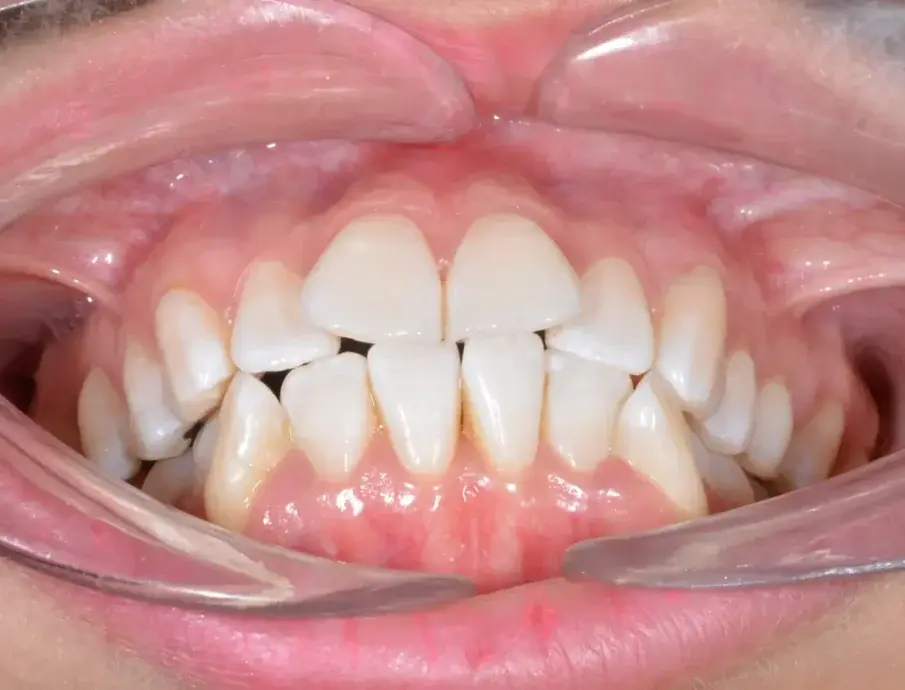

35-годишна пациентка постъпва със струпване на зъби, болки в мускулите и ставите и главоболие след събуждане. При прегледа се установява I скелетен клас със струпване и бимаксиларна протрузия. Изследването на лицето показа конвексен профил с изпъкнали устни и квадратна форма на лицето, която се засилва при усмивка (фиг. 1-4). Тя съобщава за бруксизъм и се наблюдава двустранна хипертрофия на масетерите, но няма изменения в темпоромандибуларните стави.

Фиг. 2а: Първоначални интраорални изображения.

Фиг. 2b: Първоначални интраорални изображения.

Фиг. 2c: Първоначални интраорални изображения.